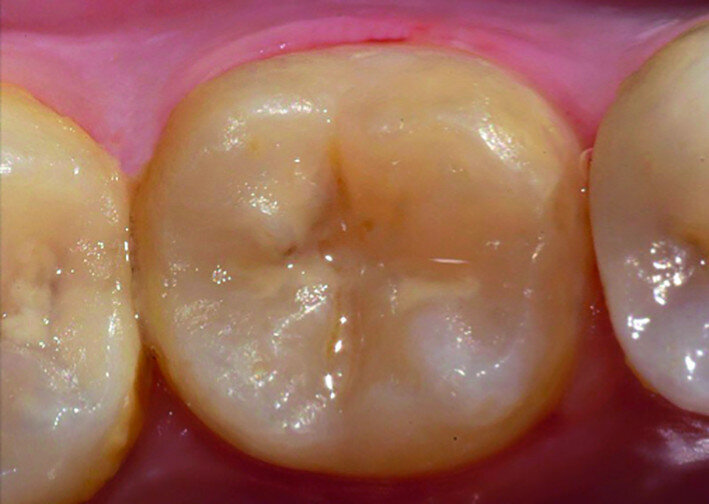

Fig. 2: Pre-op facial view.

A 47-year-old male patient in a good medical condition and a non-smoker was referred to our dental practice for endodontic retreatment of the right maxillary second molar. The dental history revealed that the tooth had been endodontically treated three months before because of acute pulpitis. After the treatment, the patient complained of pain on chewing. Antibiotics and a non-steroidal anti-inflammatory drug were prescribed, but the pain remained. After a month, a sinus tract appeared. The tooth was retreated in another practice without success. The clinical inspection revealed the presence of a sinus tract near the apical region of tooth #17. The tooth had been prepared for a full crown, but was without even a temporary crown, and the access cavity had been closed with temporary filling material. Cracks were evident on the buccal and mesial surfaces. Periodontal probing showed a deep pocket (> 12 mm) on the distal aspect of the root trunk (Figs. 1 & 2). The periapical radiograph showed a radiolucency between the roots of the second and third molars. The radiographic appearance of the endodontic treatment was good, without clear evidence of periapical radiolucencies (Fig. 3). A perforation of the pulp chamber floor was suspected. A CBCT scan was performed (Figs. 4–7), and it confirmed the suspicion of perforation, along with the presence of a large periradicular radiolucency and an unfavourable root shape.